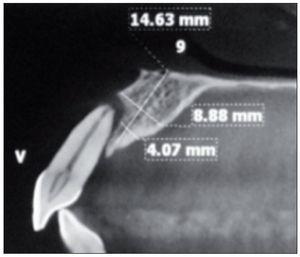

Figura 6. Tomografía computarizada de control realizada a los 6 meses.

Figura 11. Tomografía computarizada de control realizada a los 6 meses.

El implante (Superline, Dentium o Tapered Screw-Vent, Zimmer) fue instalado a los 6 meses de realizado el procedimiento de aumento tisular, previa realización de una tomografía computarizada para controlar la ganancia ósea. En 4 pacientes se realizó una técnica sin colgajo, y en los 4 casos restantes se realizó un colgajo mínimamente invasivo.

En el momento de la colocación de los implantes, se determinó el grosor del tejido blando vestibular mediante el uso de una sonda periodontal Carolina del Norte (Hu-Friedy), aproximadamente de 3 a 4 mm apical al reborde alveolar. De forma similar, se evaluó el grosor de la tabla ósea vestibular midiendo la distancia entre la plataforma del implante y el extremo más vestibular de la tabla ósea en los casos que se realizó colgajo. En los casos en que el implante fue instalado sin la realización de colgajo, se midió la distancia desde el centro del implante hasta el margen vestibular de tejido blando y se le restó el grosor de tejido blando y la mitad de la medida del diámetro del implante.

Al evaluar los tejidos en el momento de la instalación del implante, se pudo constatar que se logró un grosor de tejido duro ≥ 2 mm por vestibular de cada implante en el momento de su instalación, y a la vez se logró un adecuado grosor de tejido blando > 2 mm en relación con todos los implantes.